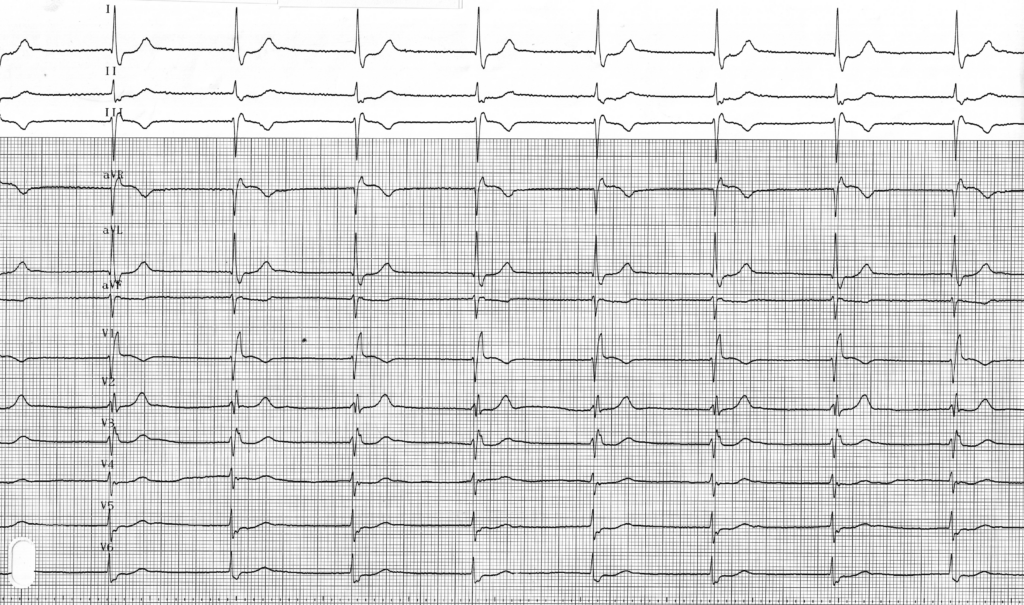

Tracé 2.3: Dysfonction sinusale, échappement jonctionnel, dyspnée d’effort

Homme de 64 ans, cardiopathie dilatée, hospitalisé pour asthénie et limitation à l’effort

Bradycardie avec fréquence à 45 battements/minute, dysfonction sinusale avec absence totale d’onde P sinusale, échappement probablement jonctionnel (QRS réguliers et modérément ralentis), avec aspect de bloc de branche droit; conduction rétrograde (activité atriale négative dans les dérivations inférieures avec intervalle RP’ fixe);

Ce patient était symptomatique avec existence d’une asthénie et d’une dyspnée d’effort. L’épreuve d’effort a permis de mettre en évidence une insuffisance chronotrope majeure avec dyspnée apparaissant dès les premiers paliers en rapport avec une absence quasi-totale d’accélération de la fréquence cardiaque et la persistance d’un échappement jonctionnel sans réapparition de l’activité sinusale normale. L’existence de cette incompétence chronotrope sans cause curable a conduit à la décision d’implantation d’un stimulateur cardiaque (indication classe I). Il existe effectivement un consensus sur le fait que l’implantation d’un stimulateur cardiaque ne modifie pas la survie des patients avec dysfonction sinusale mais permet de réduire les symptômes associés. Il n’y a donc pas en théorie d’indication chez les patients asymptomatiques (classe III).

L’insuffisance chronotrope correspond à une forme particulière de dysfonction sinusale avec apparition ou majoration de symptômes en rapport avec une accélération insuffisante de la fréquence cardiaque. L’implantation d’un stimulateur cardiaque asservi (possibilité d’accélération de la fréquence de stimulation à l’effort) en constitue le traitement de référence.